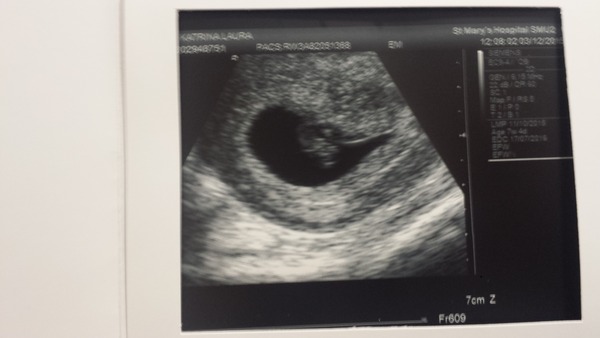

Hey everyone sorry I've not been on its been a busy day i was at the hospital for over 2 hours I had my booking appointment there as I'm under consultant care again scan went well my dates are bang on 7+2 saw the little heart beat it just looked like a little blob the scan also showed up a cyst the size of a grapefruit on my right ovary and lots of little polyps on my left ovary but I have pcos anyway so wasn't expecting any different me and my oh have sort of resolved our issues but I still want to punch in the face because he's an irritating ct excuse the language. glad your scan went well to allthegood hope everyone else is okay to I've attached a pic of my scan xx

yay! wanting looks perfect! pleased it all went well and your OH made it to the scan in the end

Wanting - lovely scan pic thanks for sharing X